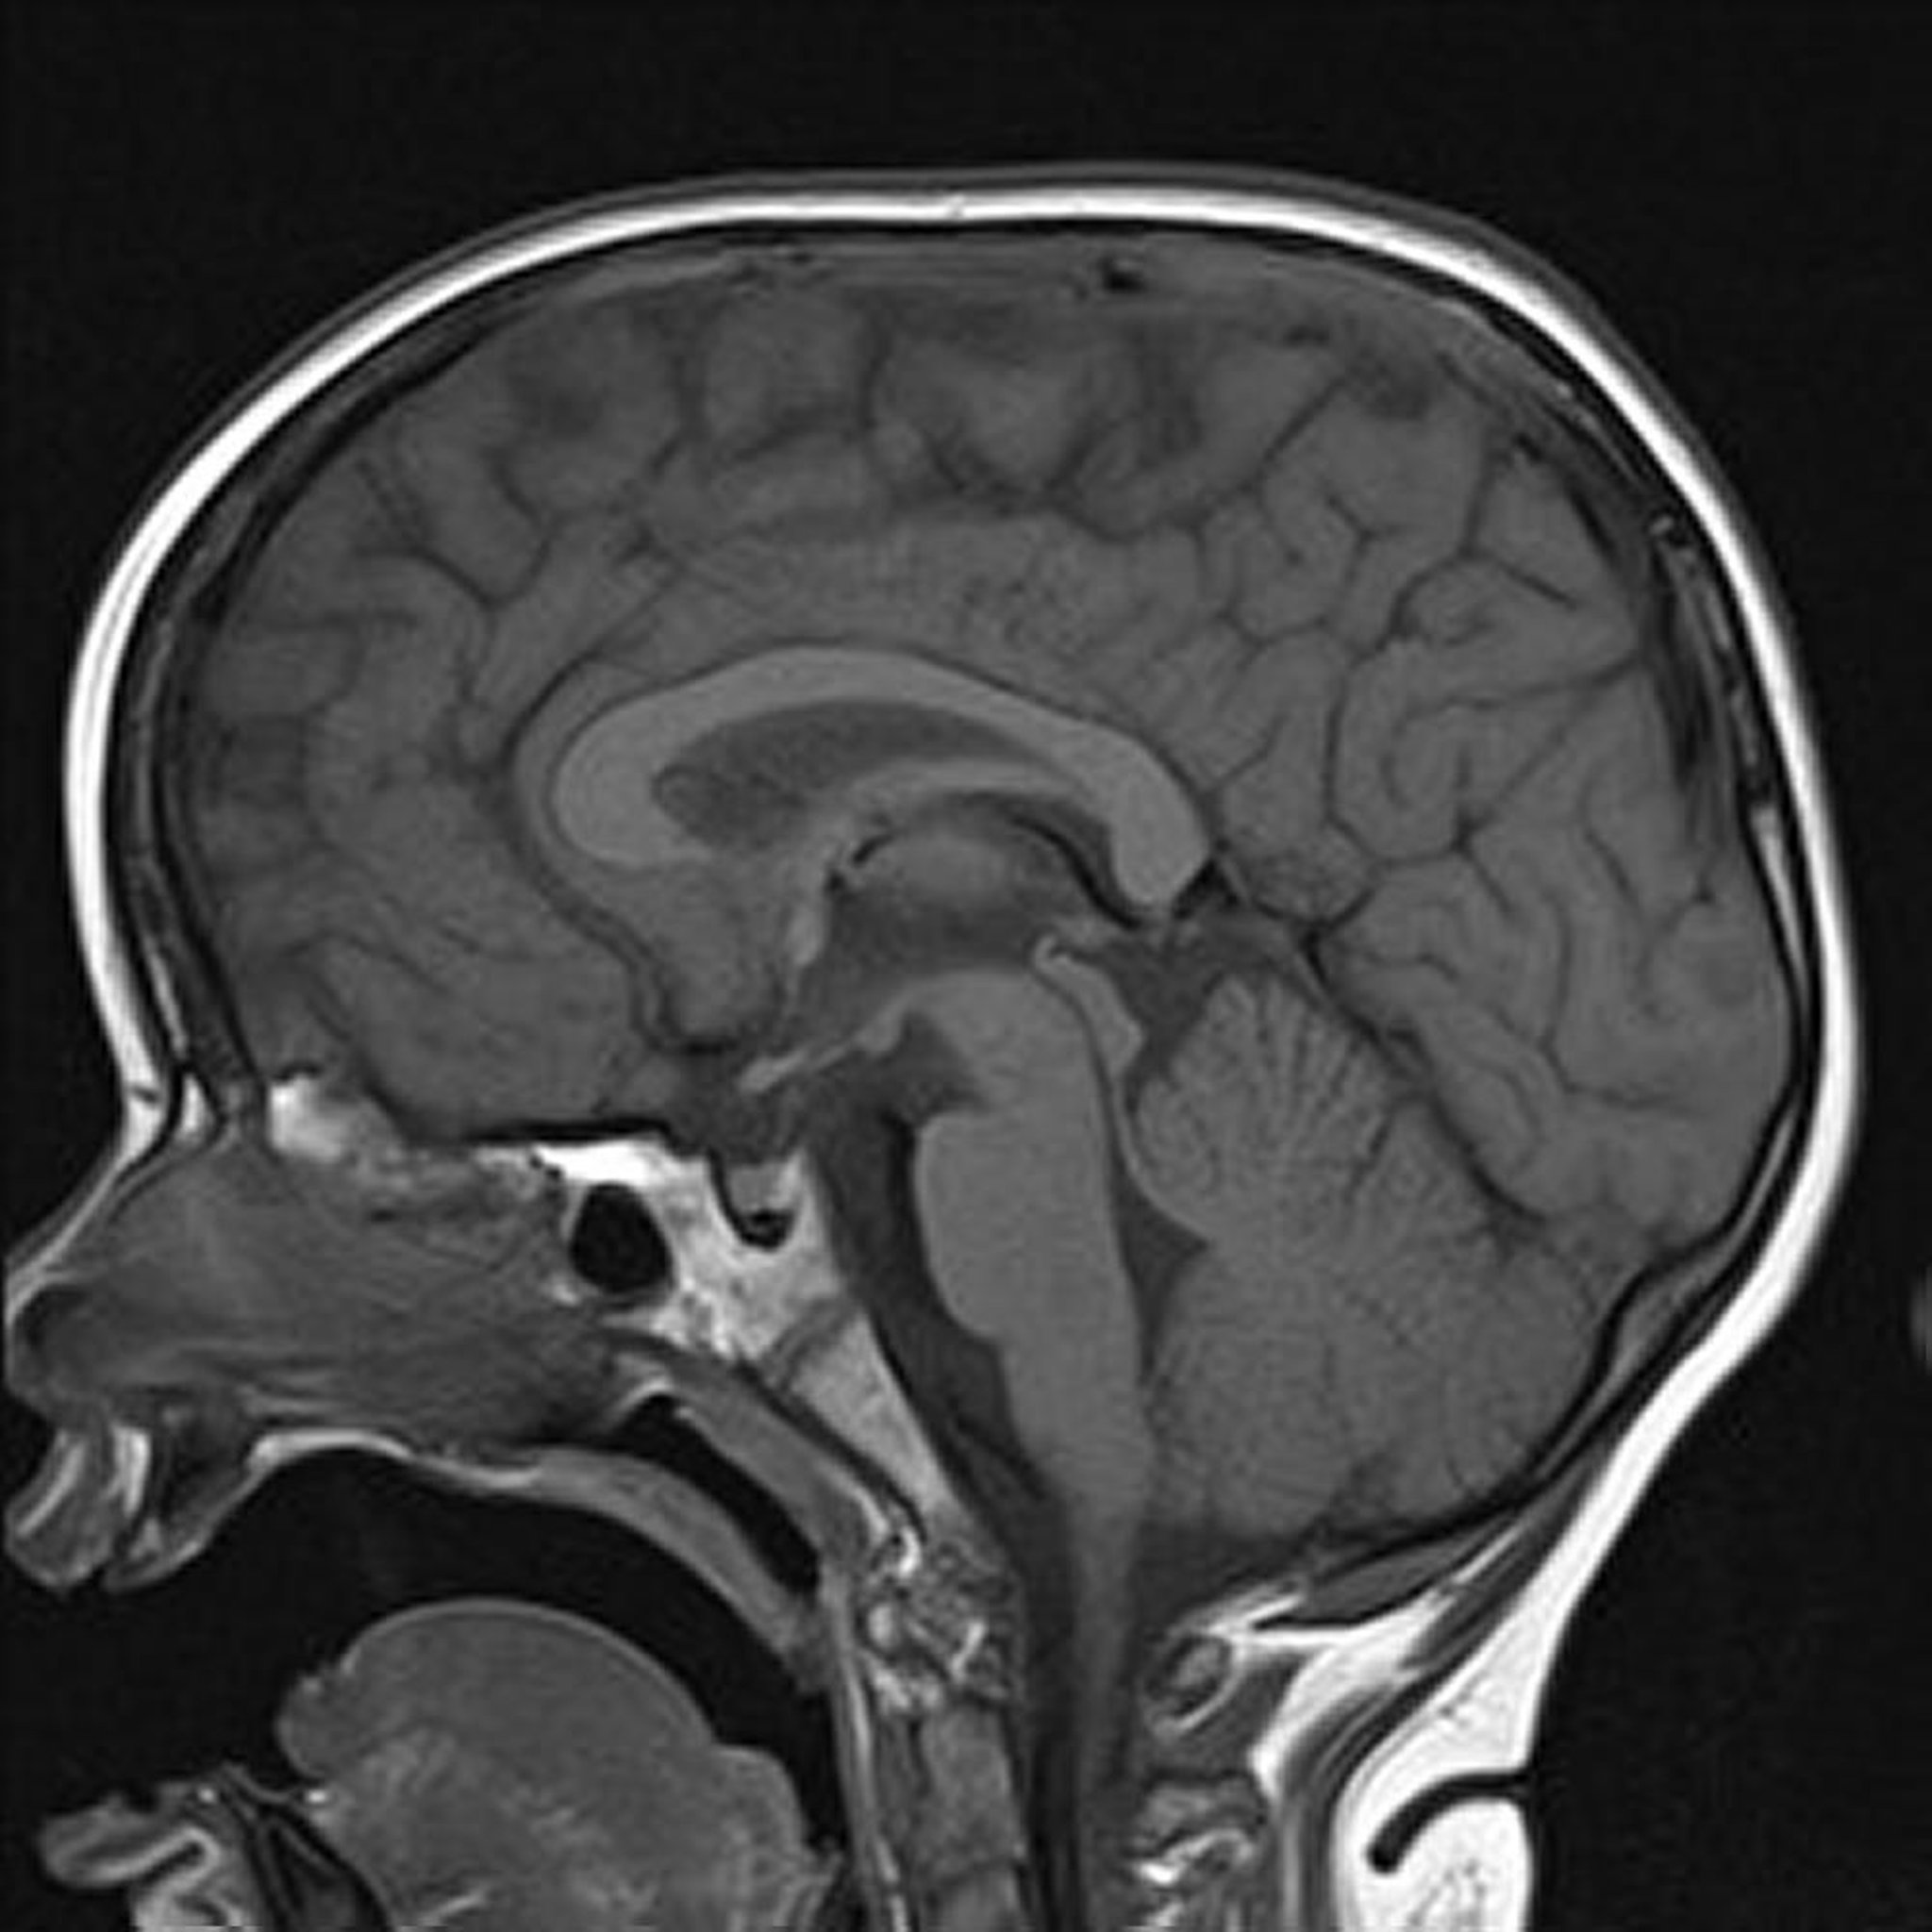

T1-gewichtetes MRT

Das sagittale T1-gewichtete Bild des Gehirns zeigt normale Mittellinienstrukturen.

Image courtesy of Hakan Ilaslan, MD.